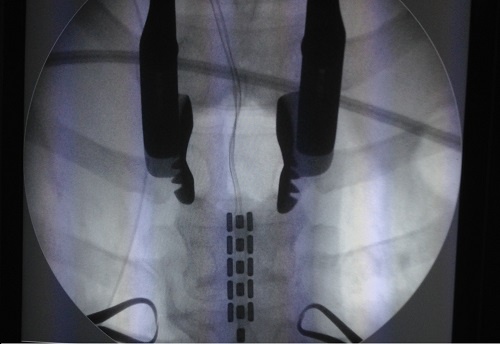

Hospital das Clínicas da UFPE moderniza cirurgias para dores na coluna

O método é indicado para pacientes com dores crônicas na coluna e é a segunda vez que este tipo de cirurgia é realizado no HC.

Mais uma cirurgia de estimulação medular foi realizada pelo Hospital das Clínicas da Universidade Federal de Pernambuco (HC-UFPE). O método é indicado para pacientes com dores crônicas na coluna e é a segunda vez que este tipo de cirurgia é realizado no HC. O procedimento, realizado na última semana de fevereiro, consiste no implante de um estimulador medular no canal vertebral conectado a uma bateria, para a emissão de pequenas descargas de intensidade regulável por meio de um controle remoto.

Coordenada pelo neurocirurgião do HC, Antônio Marco, a cirurgia reduz as dores fortes na coluna de pacientes que já não conseguem a diminuição das dores por meio de medicamentos. “Sendo realizado em uma unidade pública, este método se torna mais acessível a um número maior de pacientes que não possuem condições de arcar com os custos desta cirurgia”, ressalta o médico.

Além da cirurgia de estimulação medular, o HC também realizou no começo do ano mais uma cirurgia endoscópica percutânea lombar. O método é uma técnica minimamente invasiva para a operação na coluna e proporciona aos pacientes um menor trauma cirúrgico. A cirurgia também foi coordenada por Antônio Marco.

Indicada para pacientes que sofrem com hérnia de disco e discopatias degenerativas, a nova técnica utilizada no HC é realizada através de uma cânula cirúrgica, que deixa uma cicatriz de aproximadamente dois centímetros. “A técnica convencional para o tratamento desses problemas é mais invasiva, porém com o novo método podemos realizar a operação com uma anestesia local, um endoscópio, que proporciona uma visão clara da região que vai ser operada e uma invasão mínima, pois o procedimento é realizado através da cânula”, explica Antônio.

A nova técnica ainda permite, na maioria dos casos, que o paciente saia do hospital no mesmo dia da sua operação. “O paciente sente menos dor pós-operatória e as chances de infecção e os sangramentos durante a cirurgia são reduzidas. Isso significa que as probabilidades de complicações, durante e pós operação, diminuem”, comenta o médico sobre os benefícios do novo método. Com a cirurgia endoscópica de coluna, o HC se torna mais um hospital público a oferecer esta tecnologia aos pacientes.